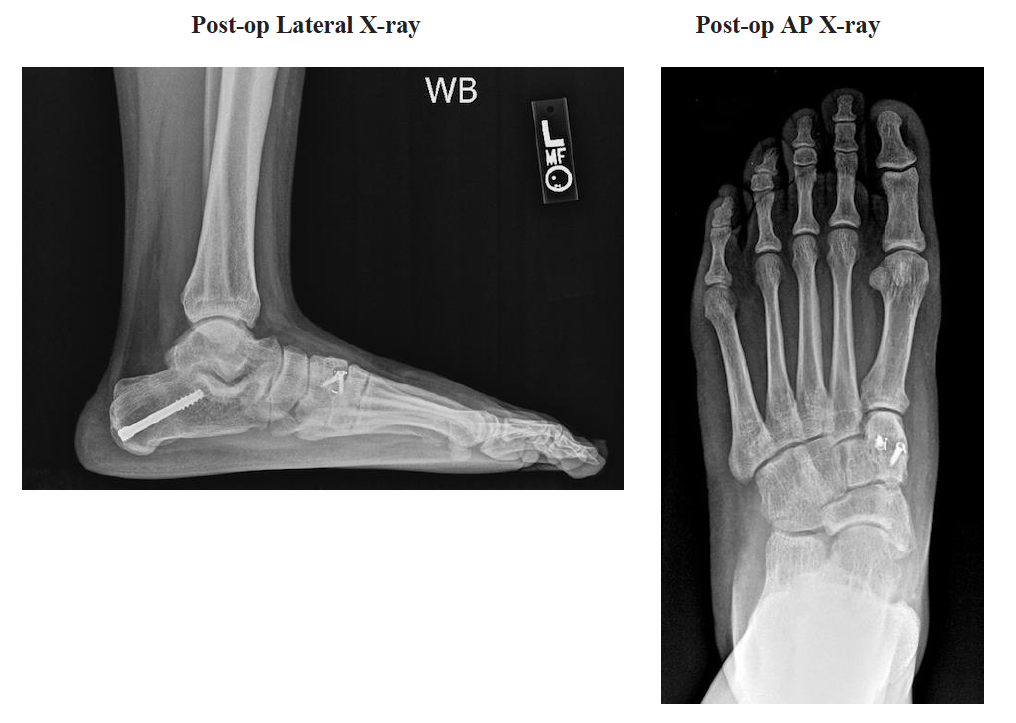

Operative Treatment: Open Gastrocnemius Lengthening, Medial Displacement Calcaneal Osteotomy, Cotton Osteotomy, Bone Marrow Aspirate, and Posterior Tibial Tenosynovectomy

Results/Conclusion: Patient was non-weight bearing for 6 weeks and then weight bearing as tolerated in a walking boot for 2 weeks. He was then transitioned into tennis shoes with custom inserts and returned to playing competitive soccer at 4 months post op. He is now 12 months out from surgical intervention with no complains, return of deformity or pain.

Surgeon Comment: The Tarsa-Link™ Stand-Alone Wedge assisted with maintaining correction of the patient’s forefoot deformity through the cotton osteotomy. Tarsa-Link’s unique design allows for low profile internal fixation through the wedge, which provides stability during the bone ingrowth process and prevents hardware irritation. The patient was able to ambulate pain free and return to competitive soccer following the procedure.